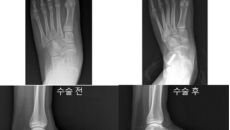

소아 평발, ‘종골 정지술’이 회복 빠르고 부담 적어

[이데일리 이순용 기자] 분당서울대병원 정형외과 성기혁 교수 연구팀이 소아 특발성 평발 환자를 대상으로 대표적인 두 수술법인- 2025.08.12 09:17